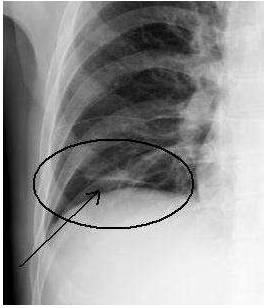

↓ 患儿9岁,咳嗽、高热。左肺炎症并左上肺肺实变、不张(X、CT)